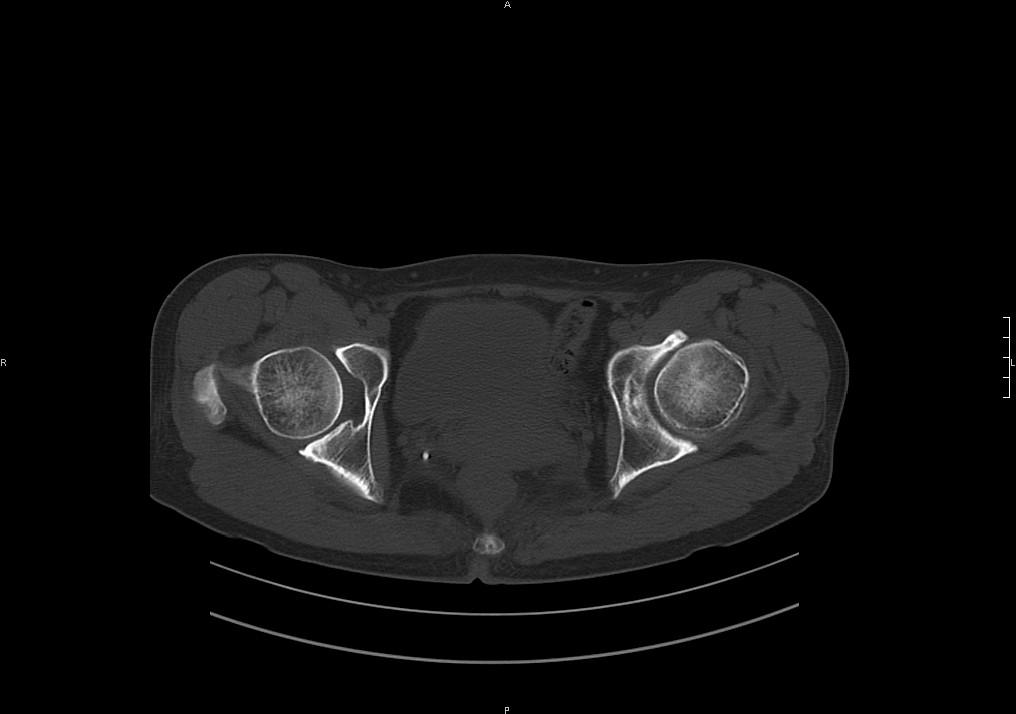

标题: CT19780左髋关节疼痛伴跛行1年,加重1个月。无菌性坏死? [打印本页]

标题: CT19780左髋关节疼痛伴跛行1年,加重1个月。无菌性坏死?

没报年龄,但髋臼有骨质增生, 考虑退行性变,坏死不明显。

髋臼平浅,股骨头覆盖率减小,考虑双侧髋关节发育不良伴退行性变。